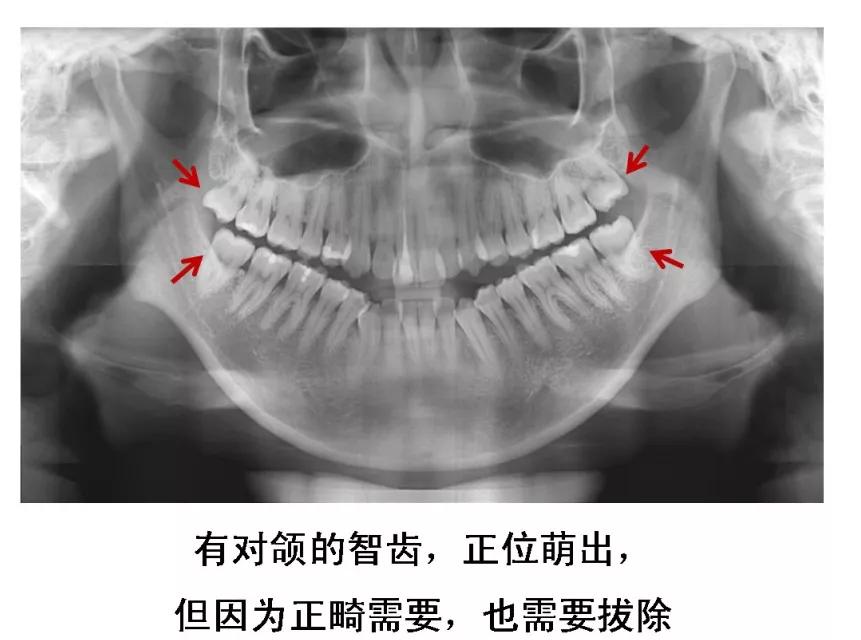

不需要拔的智齿图片_正常的智齿图片

长智齿,一定就要拔么